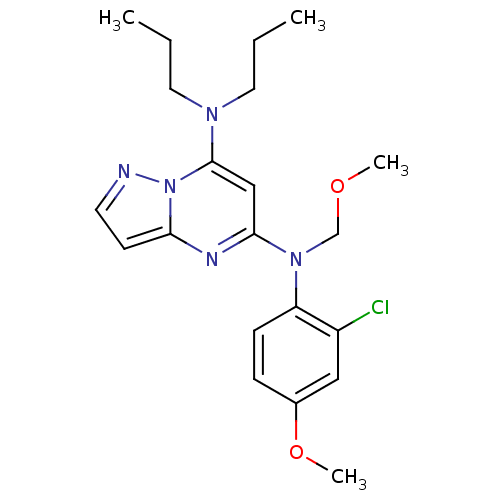

TargetCorticotropin-releasing factor receptor 1(Homo sapiens (Human))

Dupont Pharmaceuticals

Curated by ChEMBL

Dupont Pharmaceuticals

Curated by ChEMBL

Affinity DataEC50: 1.10nMAssay Description:Antagonist activity at human CRFR1 expressed in HEK293 cells assessed as inhibition of sauvagine-induced cAMP accumulation by measuring sauvagine EC5...More data for this Ligand-Target Pair